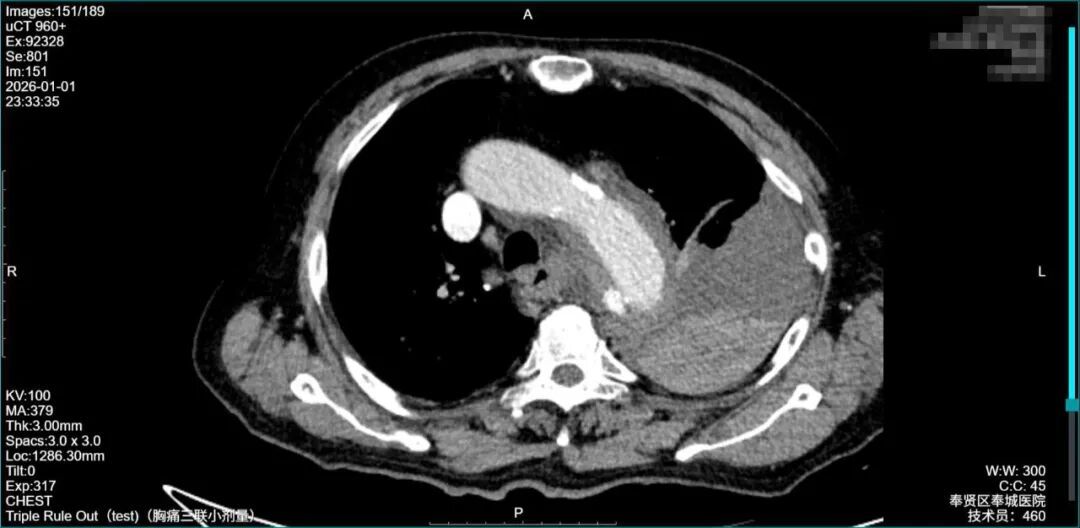

急诊团队凭借多年急危重症救治经验,瞬间判断这绝非普通胸痛!“立刻启动紧急救治绿色通道!”随着指令下达,吸氧、补液、心电监护等一系列生命支持措施同步进行。在患者血压极不稳定、无法长时间耐受检查的情况下,影像科团队火速到位,急诊增强CT血管成像(CTA)仅用15分钟就锁定“元凶”:主动脉夹层(StanfordB型)破裂!血液已涌入纵隔及左侧胸腔,形成巨大血肿,如同“血管破了个大洞”,每分每秒都在吞噬生命。

术后影像显示:覆膜支架定位精准,主动脉破口被完全隔绝,血管血流恢复正常!